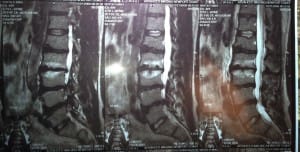

Dr. Mike’s Lumbar MRI – 4 herniated discs

Foot drop can be a scary thing to have. Back in 1997 I developed foot drop due to 4 herniated discs in my lumbar spine. My right foot felt like I could barely lift it up and I was conscious of every step I took with my right leg. I finally had to sell my practice in Santa Barbara and take some time off of bending over patients as it was definitely making my symptoms worse. My Foot Drop Treatment consisted of specific Gonstead Chiropractic Adjustments; Cryotherapy; Spinal Exercises including stretching and strengthening; Class IV Laser Therapy and improved posture and biomechanics I have regained my foot strength and made a full recovery.